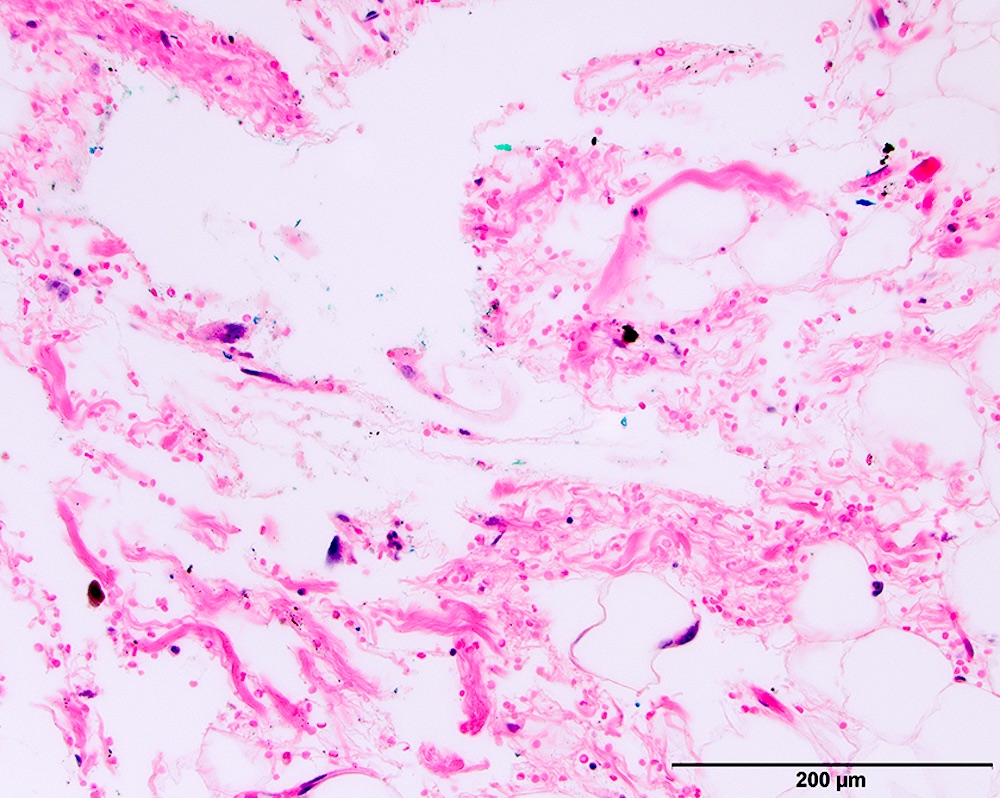

Microscopic (histologic) images

Contributed by Michael Clay, M.D., Melanie Bourgeau, M.D. and AFIP

Morphologic variability:

Metaplastic change:

- ALT / WDL with low grade osteosarcoma-like areas

- In contrast to osseous metaplasia, these lesions have foci reminiscent of parosteal osteosarcoma or low grade central osteosarcoma (Am J Surg Pathol 2010;34:1361)